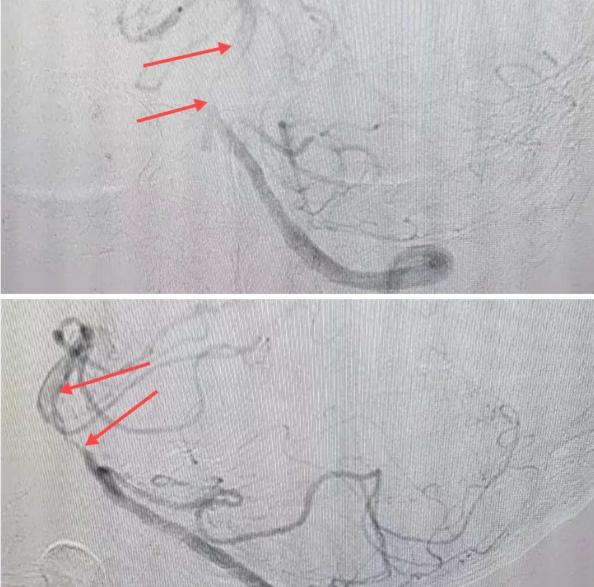

在經(jīng)造影后,主刀醫(yī)生腦一科副主任楊慶堂發(fā)現(xiàn)患者基底動(dòng)脈下段重度狹窄且狹窄段以遠(yuǎn)有大負(fù)荷血栓,其狹窄處考慮為動(dòng)脈夾層,手術(shù)難度及風(fēng)險(xiǎn)較大。楊慶堂副主任在彭壯副主任醫(yī)師的協(xié)助下運(yùn)用spaceman(太空人)技術(shù),中間導(dǎo)管抵近血栓抽吸配合支架拉栓,成功開(kāi)通血管。再次造影可見(jiàn)基底動(dòng)脈管腔明顯增寬,遠(yuǎn)端血管顯影良好,且等待20分鐘后造影仍顯示血流通暢。楊慶堂副主任考慮到本次手術(shù)時(shí)間不宜過(guò)長(zhǎng),現(xiàn)患者基底動(dòng)脈及分支前向血流維持良好,給予其抗栓藥物應(yīng)用后結(jié)束手術(shù),并建議患者3個(gè)月后復(fù)查造影,明確其基底動(dòng)脈夾層情況。

造影可見(jiàn)血管夾層和大量血栓形成

取栓后血管管腔增寬,前向血流良好